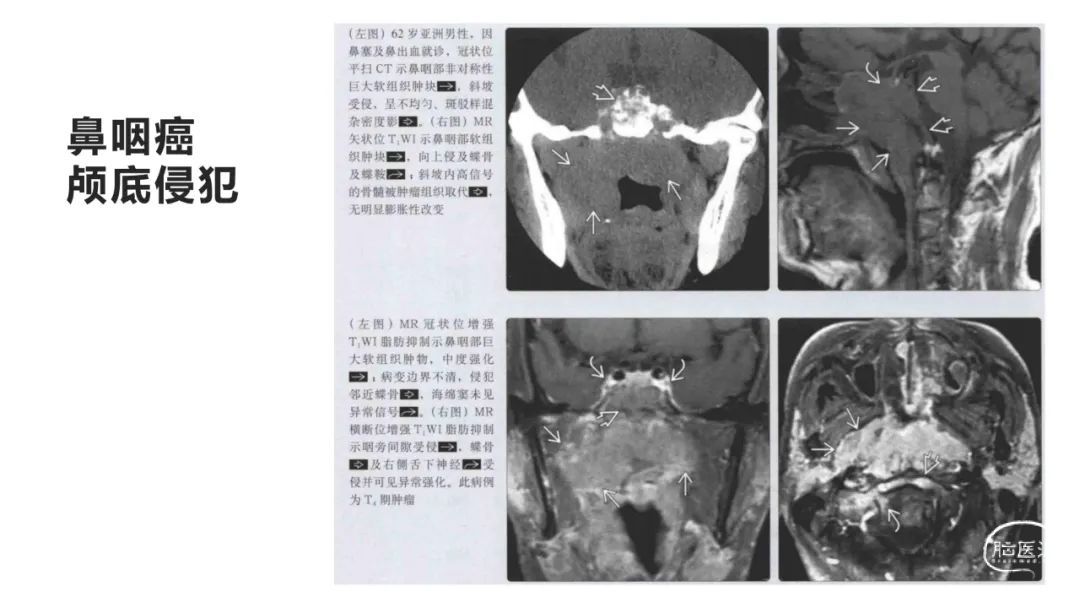

颅脑影像诊断基础知识讲座:颅骨病变